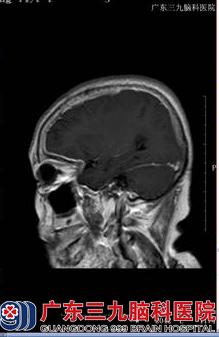

71岁的刘某本可在家安度晚年,坐享天伦之乐,可是,就在一年多前,她出现了右侧头部疼痛,阵发性枕部牵拉痛,持续数分钟至数小时不等,每天上午约11时出现剧烈疼痛,到相关医院进行眼眶CT示双侧眼球内斜位,头颅MRI+MRA示右侧额叶、基底多发性腔梗,右侧中后组筛窦、蝶窦,暂考虑炎症,由于刘某还出现了视力下降,在眼科医院眼球彩超室双侧玻璃体混浊(+)伴后脱位。脑脊液常规示白细胞17*106/L,脑脊液生化示蛋白0.87g/L,颅脑MR增强示双侧大脑及小脑幕脑膜增厚,右侧明显,考虑一个脑膜炎,给予相关治疗后,效果差,2014年10月,刘某左眼亦出现视力下降,到其他医院行头颅MRI+增强示弥漫性硬脑膜强化并右额颞部硬膜下小血肿,脑脊液常规示白细胞20*106/L,脑脊液生化示蛋白1.714g/L,再接受相关治疗后,刘某仍感不适,遂到广东三九脑科医院进一步治疗。

收治入院后,完善相关检查发现:患者意识清楚,懒言少语,言语不清,记忆力、计算力、定向力等认知功能下降,MMSE13分(存在认知功能障碍),右侧眼裂小,右眼失明,右侧瞳孔扩大,直接对光反射迟钝;左侧瞳孔正常,直接对光反射稍迟钝,余脑神经(-),双下肢肌力五级弱,肌张力正常,双侧腱反射(++),左侧Babinski征、Chaddock征均(+),颈部绵软,Kernig征、Brudzinski征均(-),双侧指鼻试验、快复轮替动作及跟膝胫试验均完成。故初步诊断为:1、头痛查因:硬脑膜炎(特发性肥厚性)?2、脑梗死?3、硬膜下血肿(恢复期)?神经内二科王展航主任在详细了解病人病情后,制定了详细的治疗方案,给予病人改善脑循环、神经营养、激素、康复治疗等加强对症支持治疗。

【头颅MRI结果】: